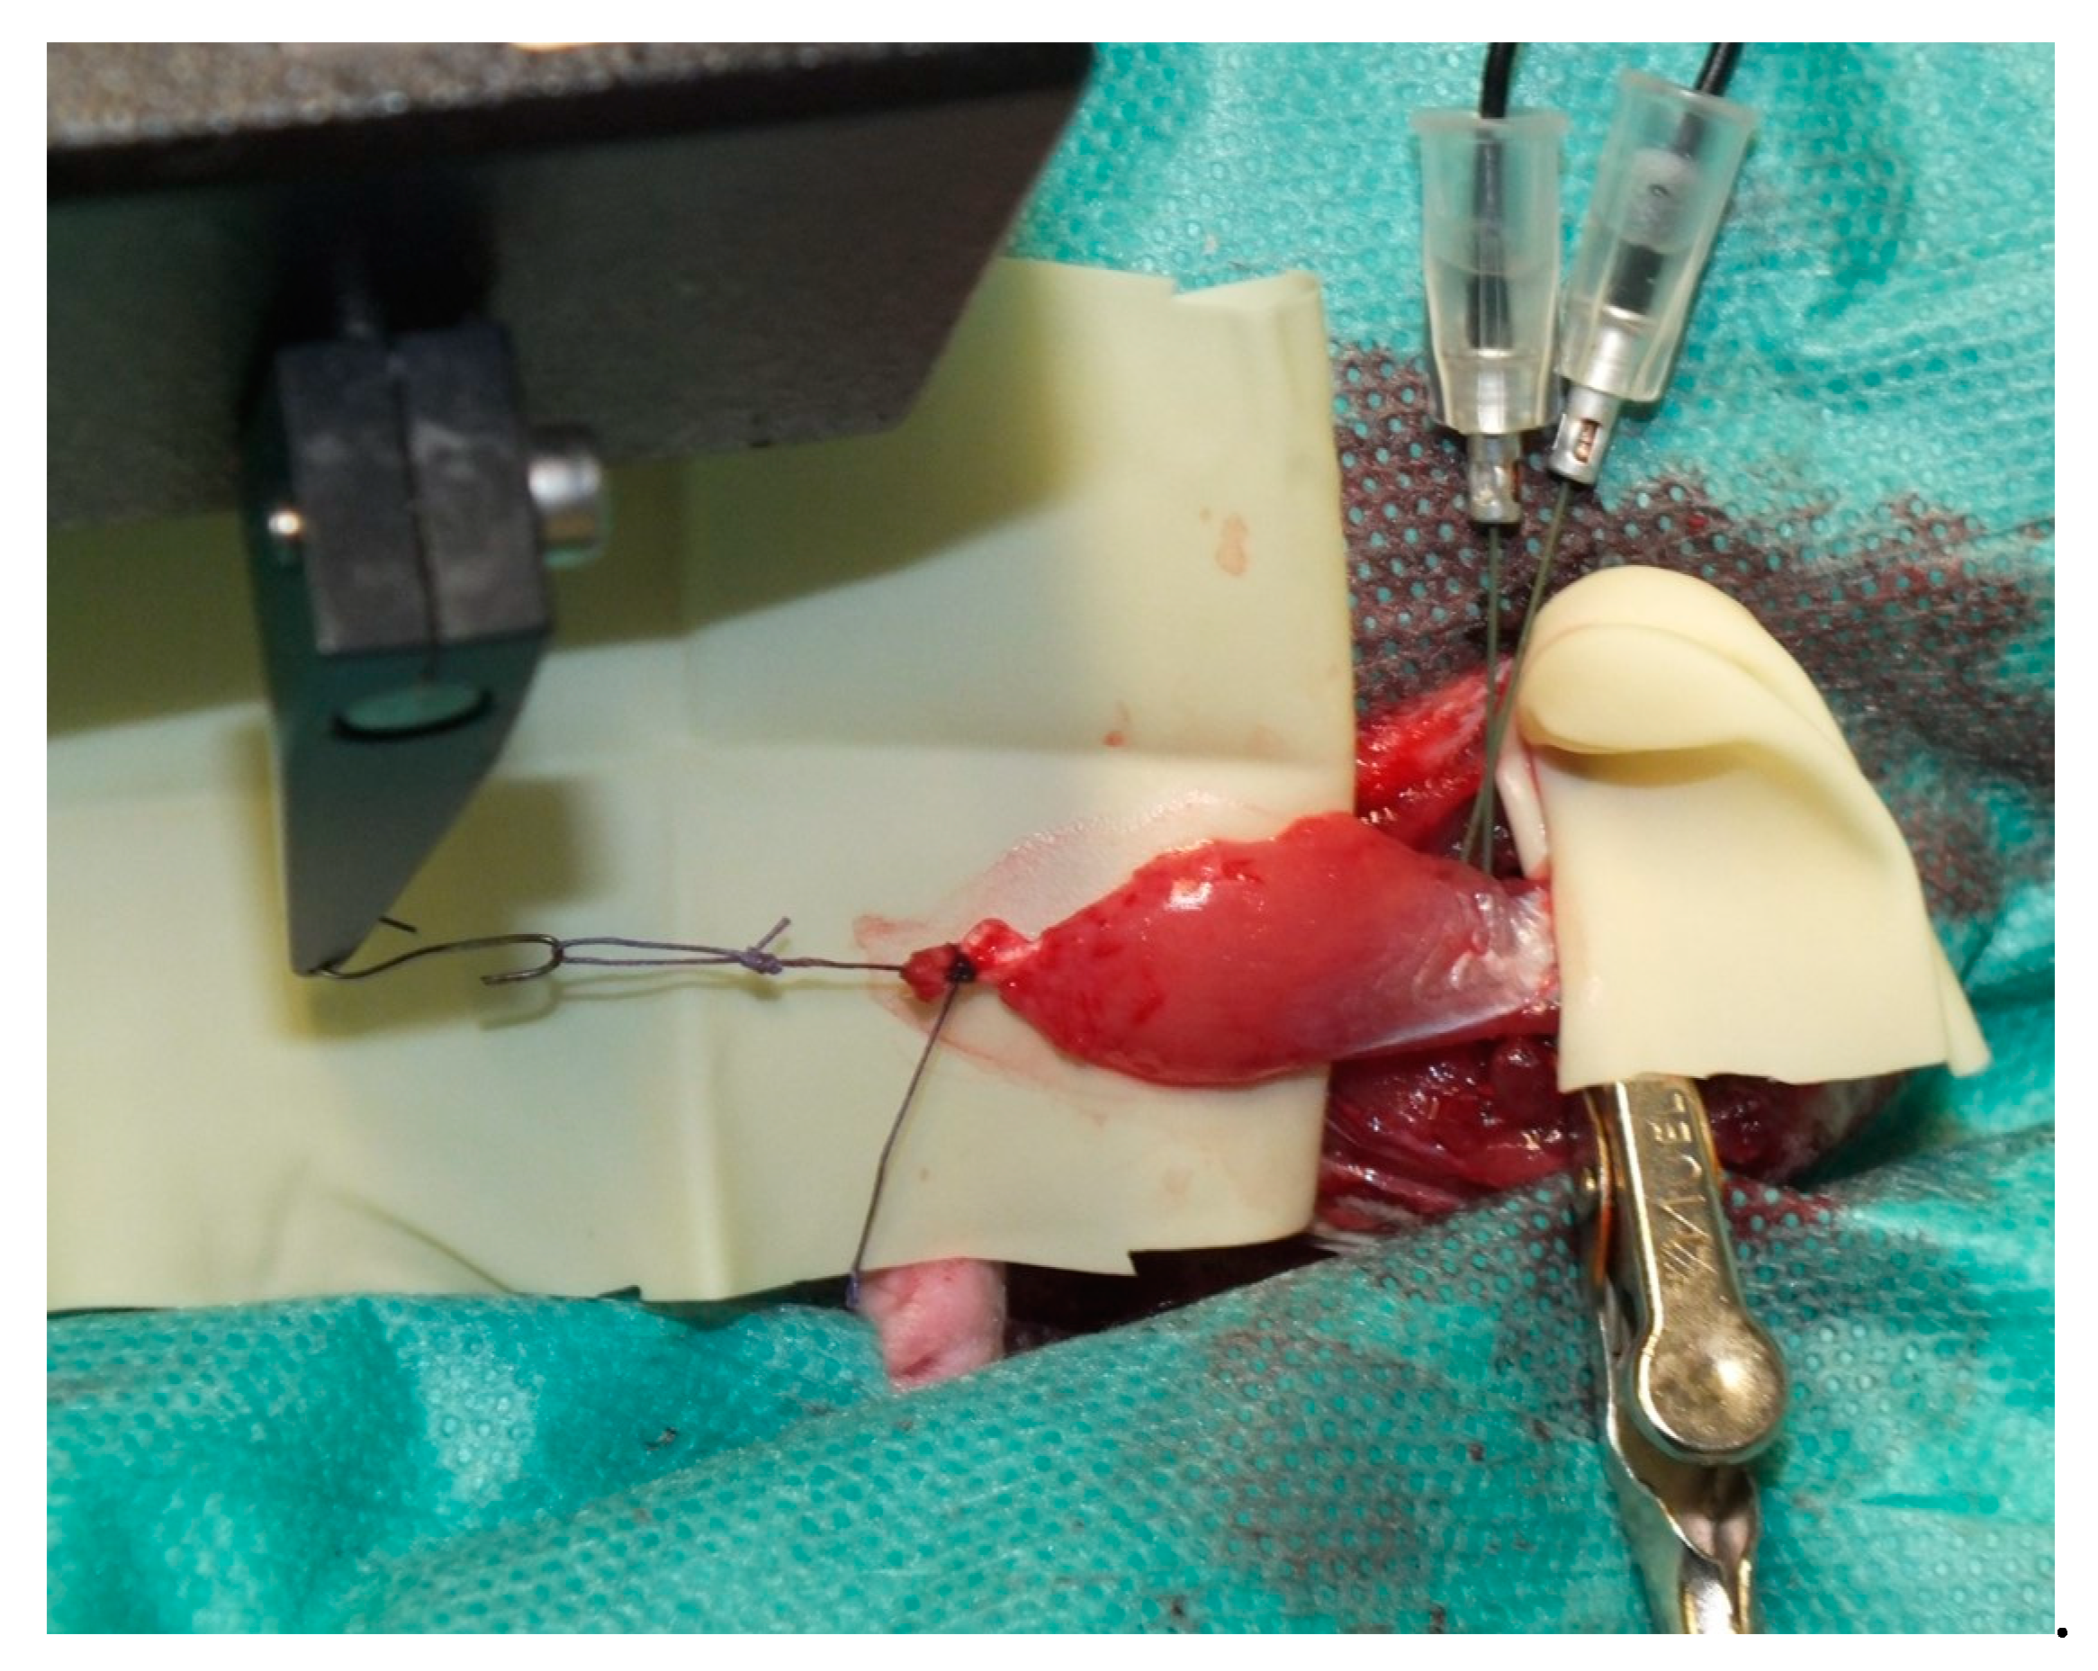

2.2. Muscle Preparation

2.4. Muscle Transplantation

3.1. Surgery and Animals